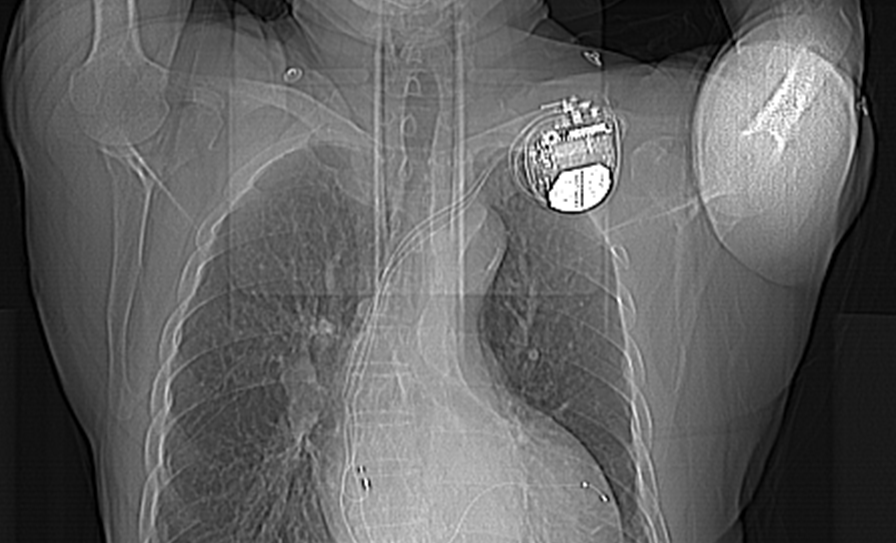

医 术 2021年9月6日 成都东篱医院 心内科李其勇主任带领科室团队 为一位患“扩张型心肌病 ”七十岁爷爷 成功施行“ CRTD植入术” 希望可以治好自己的“心病” 夏爷爷,70岁,十余年前就因活动后心累气促、活动耐受力下降,被当地医院诊断为“心力衰竭”,给予药物治疗后好转。近些年反复发作,后被诊断为“扩张型心肌病 全心增大 EF下降型心衰”,辗转于多家医院,治疗效果微乎其微。1个月前夏爷爷感到病情进一步加重,甚至走几分钟的路都得停一停、缓一缓,身体乏力,精神萎靡,夜间还存在呼吸困难的情况,于8月27日收入我院心内科。 心脏彩色多普勒超声提示:LA55*73*62,LV76,RA59*42,IVS11,EF37%。 腔内电生理图提示:QRS波163.89ms 新技术带来新希望 术前科室医疗组经过反复分析病情与家属沟通后,决定为夏爷爷植入CRTD(心脏再同步化治疗及埋藏式心脏自动除颤器)。 CRT(心脏再同步化治疗起搏器)可以保证心脏的左右心腔重新恢复同步收缩,减少由于心脏扩大导致的瓣膜返流,达到改善心衰,逆转心脏扩大的作用。 ICD(埋藏式心脏自动除颤器)则可以自动识别室性心动过速、室性纤颤等恶性快速心律失常,及时给予电学终止治疗。 CRTD将以上两种功能合二为一,该技术集起搏、治疗恶性心律失常、改善心力衰竭于一体,使慢性心衰病人恢复双心室同步收缩、改善心功能、从而降低心律失常的发作,提高生活质量,降低心衰住院率和死亡率。 CRTD成功植入,老人平安 手术器械的选择,手术的每一个步骤,术中可能出现的危急情况等,科室都做了充分的准备。9月6日,在李其勇主任的指导下,心内科医护团队紧密协作,克服患者靶血管相对细小的困难,最终选择适宜位点,成功植入电极,手术非常顺利。 安置后的CRTD 术后经胸部CT证实患者电级安装到位,程控起搏器各项数据工作良好。切口周围皮肤无红肿、无明显活动性出血疼痛,患者自述症状较前期缓解。从此,夏爷爷的心脏有了一个“新管家”,心功能将逐渐恢复!